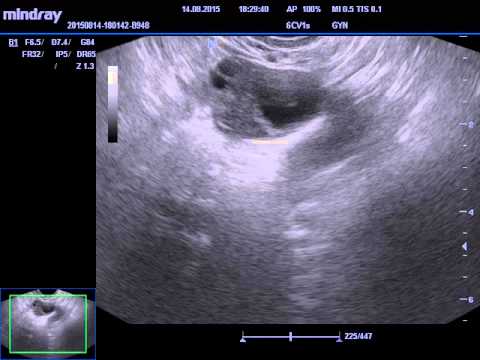

Ультразвуковая фолликулометрия проводится с помощью ультразвуковых волн, которые безопасны для организма и позволяют получить визуальное изображение женских внутренних органов. Может быть проведена как через брюшную стенку с обычным датчиком, так и трансвагинальным датчиком, вводимым во влагалище. Процедура является безболезненной, но может вызывать незначительный дискомфорт. Результаты оцениваются врачом и предоставляются для дальнейшего лечения.